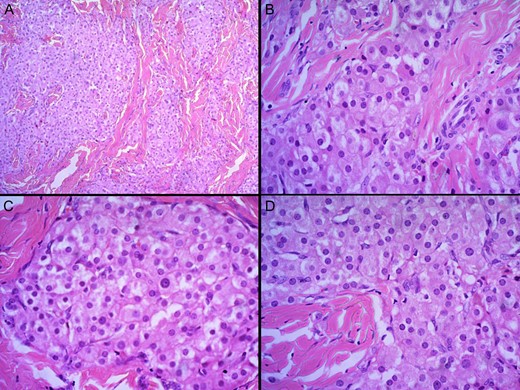

A biopsy of the right epididymis was performed. The sections revealed nodules of cells with intervening dense fibrous septae. The nodules comprised nests and cords of polygonal Leydig cells with abundant eosinophilic cytoplasm, uniform round nuclei and small nucleoli. Cell borders were distinct and a lymphoid infiltrate was present in the stroma (Fig. 1). Testicular tissue comprised of seminiferous tubules with thickened basement membranes. Residual testicular tissue showed predominantly germ cell aplasia with occasional tubules containing spermatogonia. Most seminiferous tubules contained only Sertoli cells. Spermatocytes, spermatids and spermatozoa were absent. Collections of Leydig cells were noted between the seminiferous tubules. Intratubular germ cell neoplasia or malignancy was absent (Fig. 2).

H and E staining viewed under ×4 (A) and ×40 (B) showing testicular tissue comprised of seminiferous tubules with thickened basement membranes. Residual testicular tissue showed predominantly germ cell aplasia with an occasional tubule containing spermatogonia.